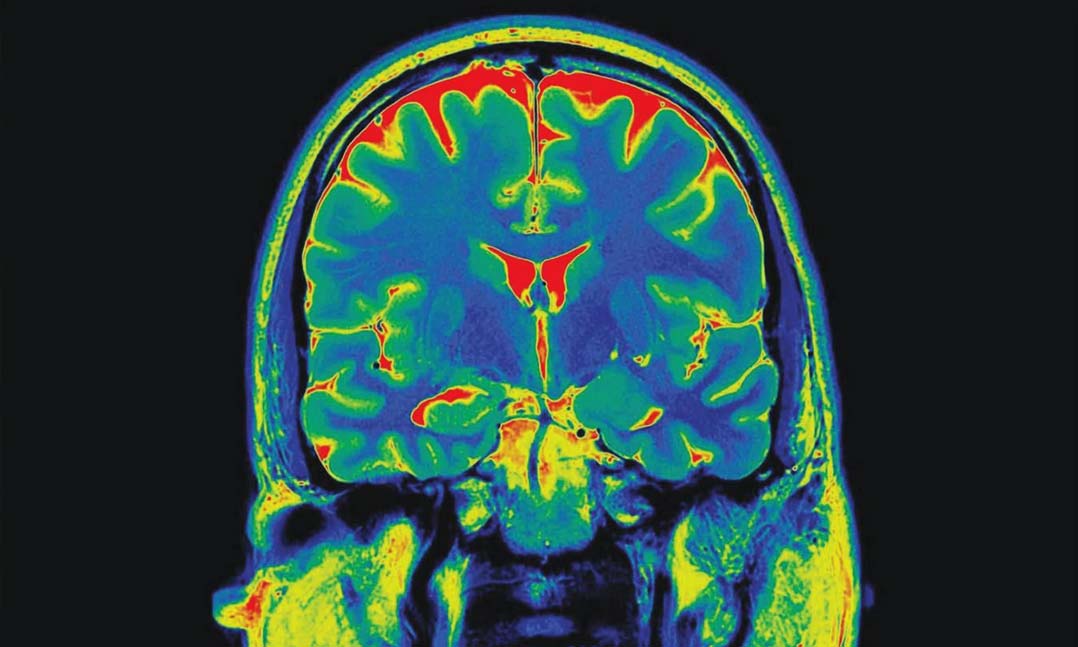

Brain scanTo research, scientists from the VA Connecticut Healthcare System, Icahn School of Medicine at Mount Sinai, Israel’s Ben-Gurion University of the Negev and the Yale University School of Medicine observed brain activities of 28 people — 11 women and 17 men — with an average age of 38. PTSD patients shared three types of memories:

Researchers turned each patient’s recollection into an audio script narrated by another person. Patients received an MRI while presented with a summary of their own experiences. Scientists observed that the PTSD patients experienced “traumatic” memories in a different part of the brain than “sad” and “calm” memories.

The memories of “sad” and “calm” events, according to the study, triggered the brain’s hippocampus, which is known to play a role in long-term memory. However, researchers found that during the re-experiencing of traumatic events, the posterior cingulate cortex (PCC) was stimulated in the patients’ brains.

“The brain does not treat traumatic memories as regular memories, or perhaps even as memories at all,” Schiller said. “We observed that brain regions known to be involved in memory are not activated when recalling a traumatic experience. This finding provides a neural target and focuses the goals of returning traumatic memories into a brain state akin to regular memory processing.”